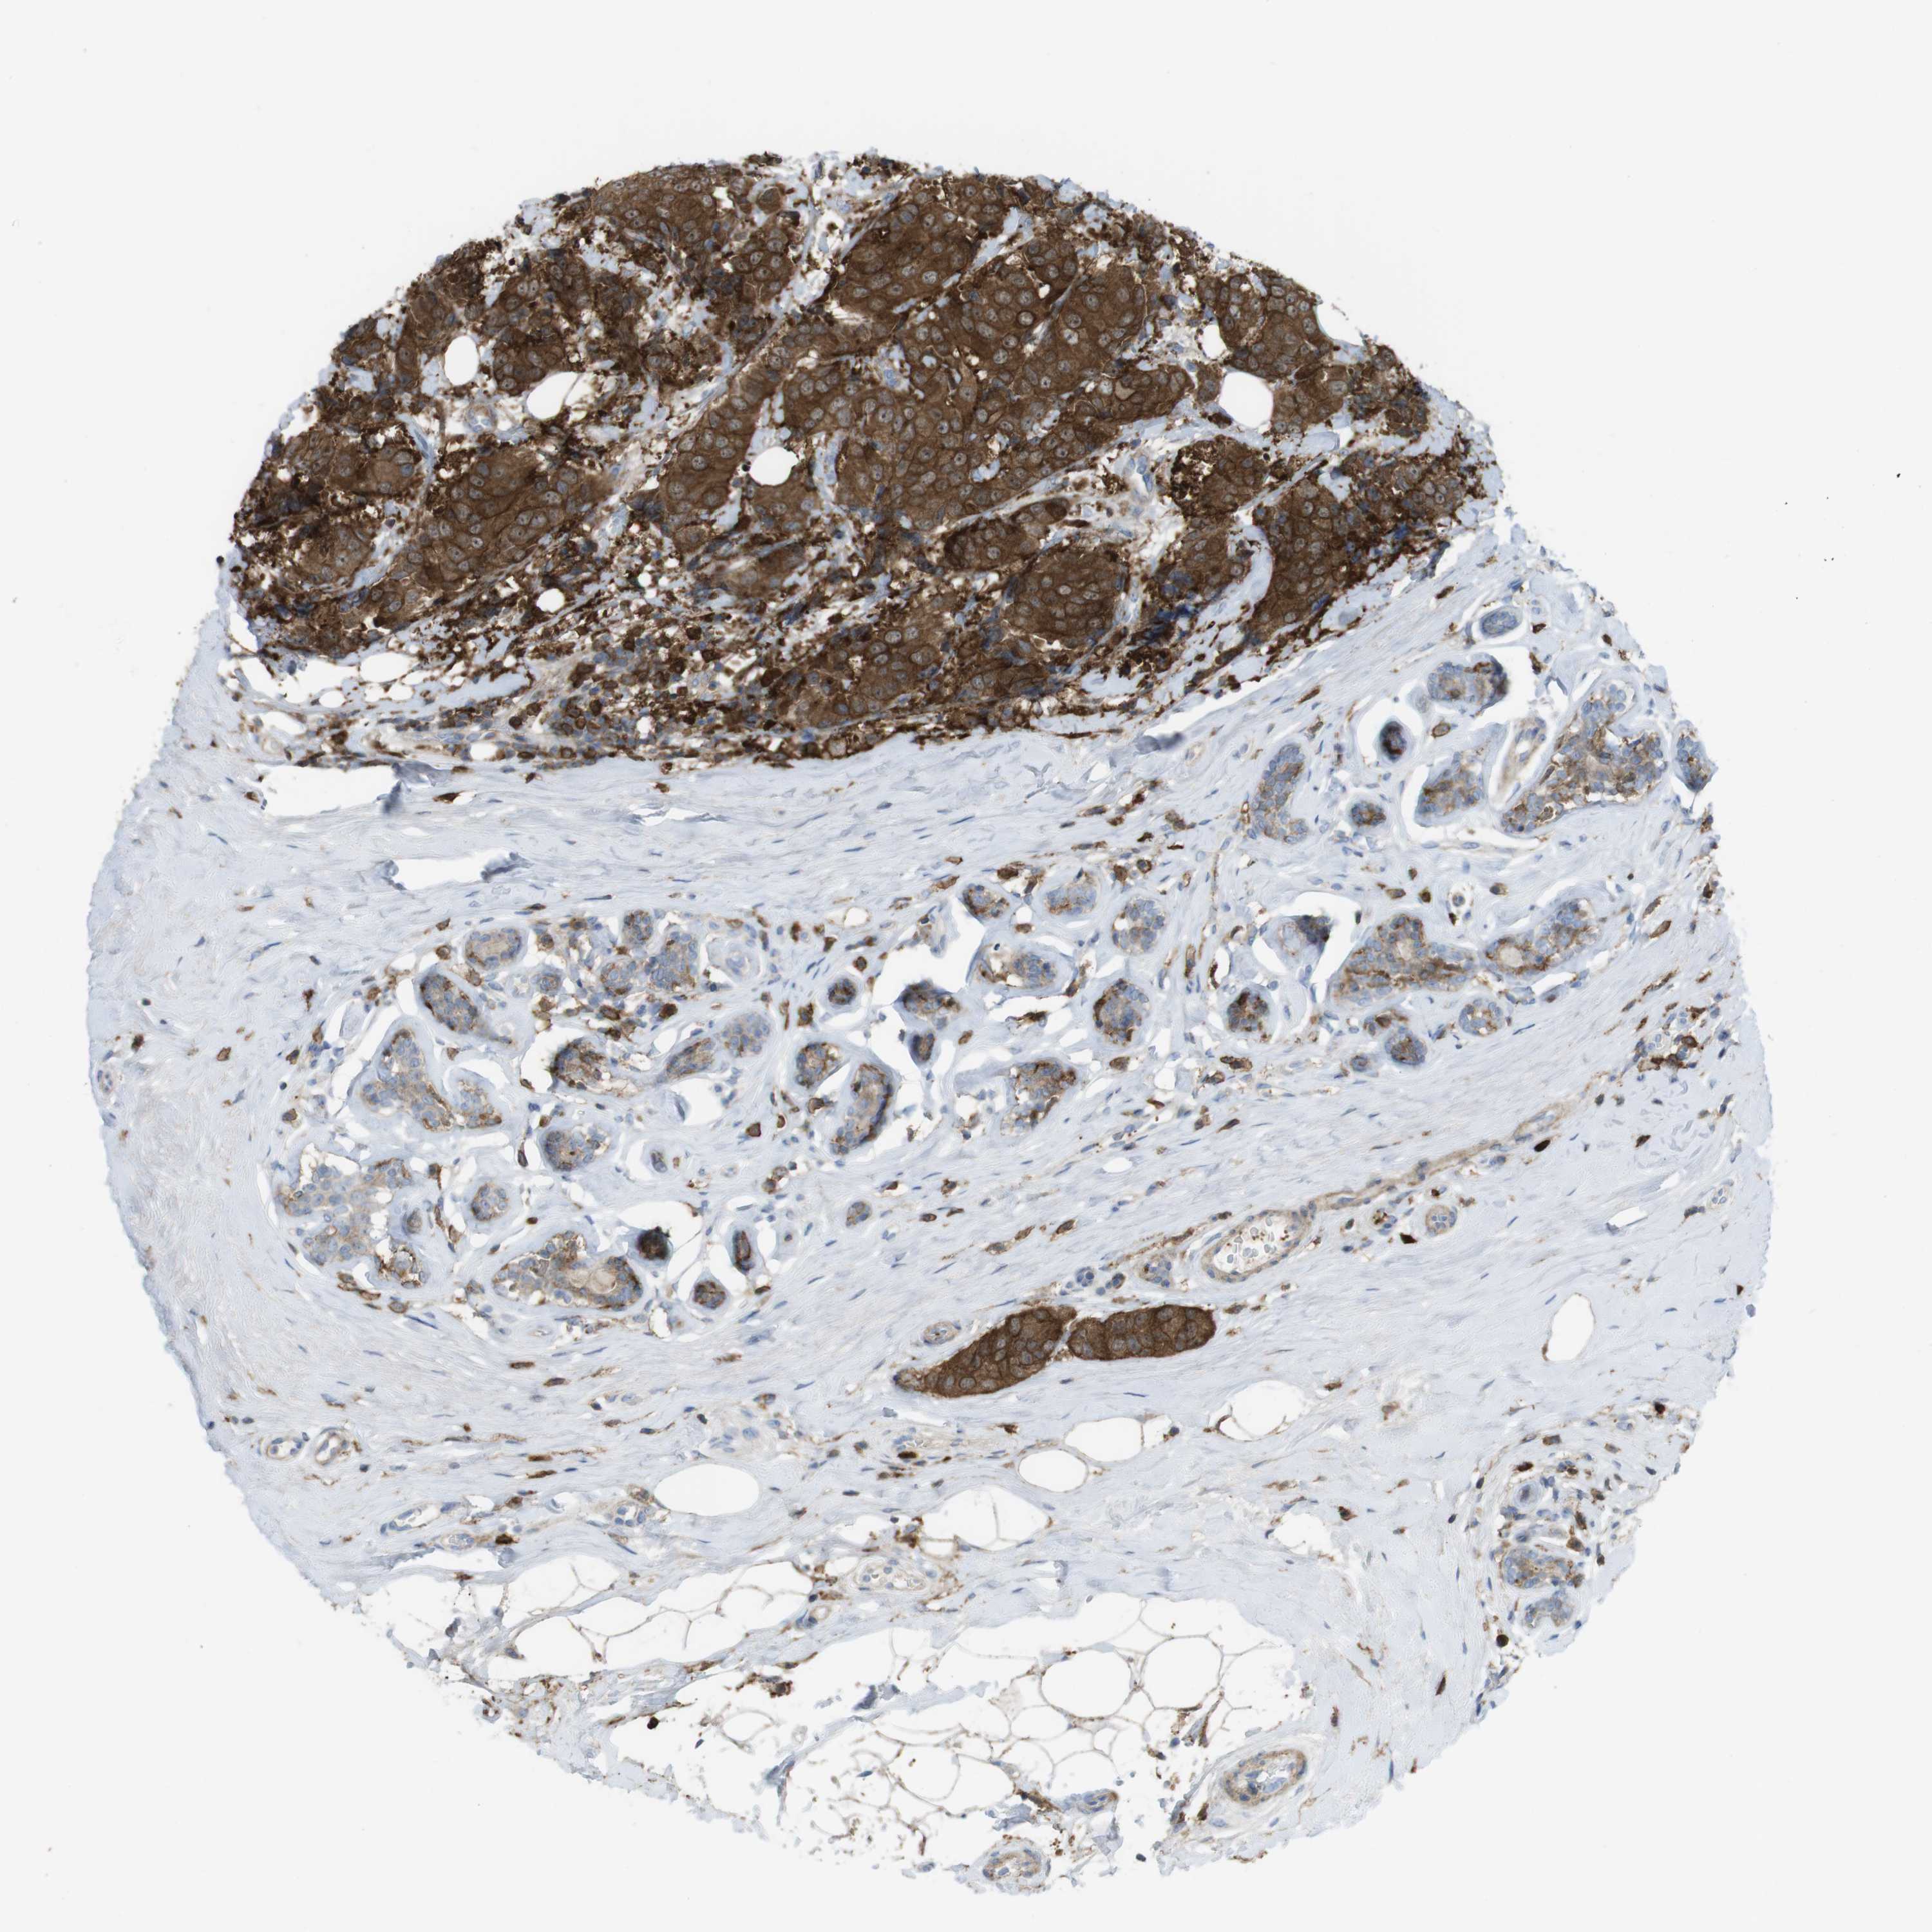

CANCER BREAST CANCER Show tissue menu

BRCA TCGA BRCA VALIDATION PROTEIN EXPRESSION

ANTIBODIES

AND

VALIDATION